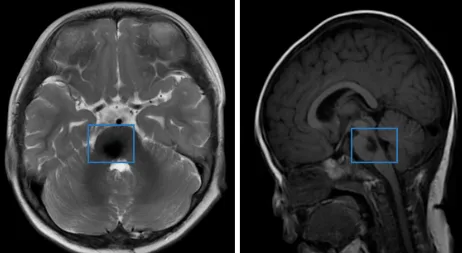

头颅核磁共振检查的结果很快就出来了:第四脑室底部占位性病变,考虑室管膜瘤可能性大。影像学特征提示肿瘤与脑干解剖关系密切,存在潜在的手术风险。

术后,我们遵照医嘱接受了辅助性质子放射治疗,以期控制可能残留的病灶。然而,治疗结束后的影像学评估显示:残留肿瘤对放疗不敏感,病灶体积未见明显缩小。

欢欢被推进手术室后,我在外面的长椅上坐下,望着窗外的云朵。不知过了多久,巴教授穿着手术服走出来,神情显得放松了一些。他说:“肿瘤已经全切了,一切顺利。”